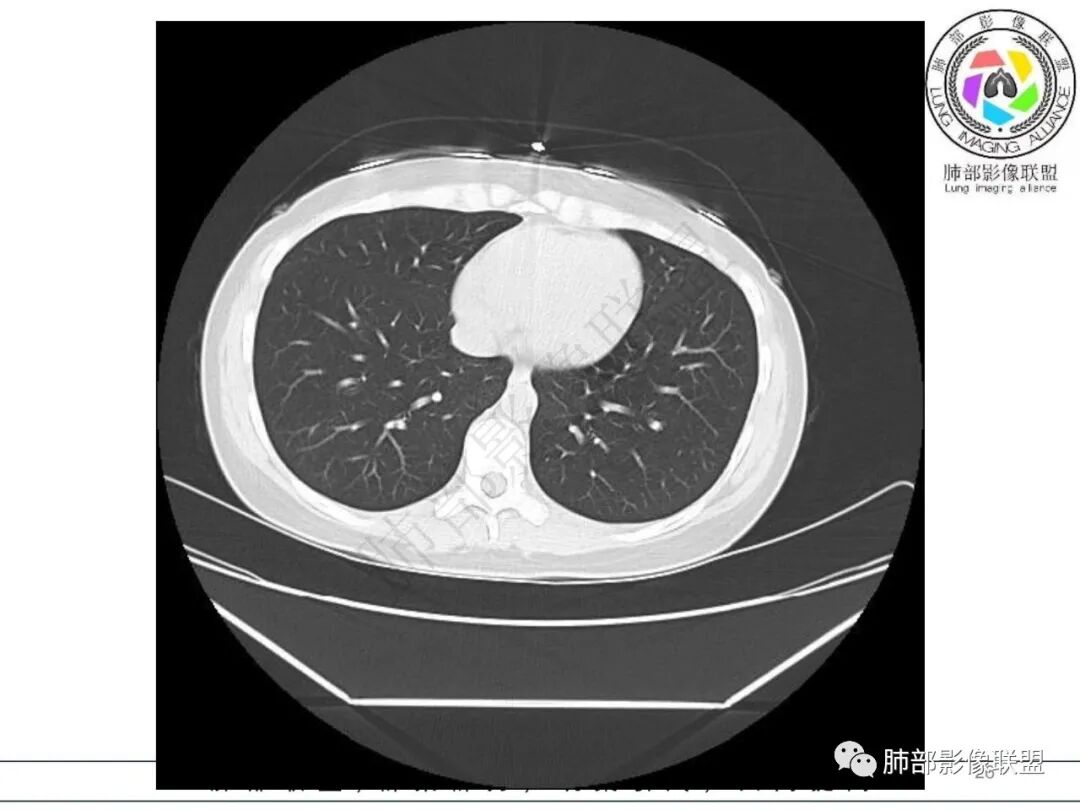

2.影像特征:右肺下叶局限性实变影伴晕征,边界不清,内部支气管尚通畅,实变区密实区边缘稍膨隆。符合炎性病灶特征。

3.综合分析:急性病程,炎性指标高,常见的是普通社区肺炎,如肺炎链球菌感染等。但本例患者临床表现较重,应先表现相对较轻,白细胞不高,须考虑非典型肺炎的可能性。本例隐球菌荚膜实验阴性,而军团菌临床症状一般较重,影像分布也更广泛、进展迅速,多器官损害更明显。因此考虑鹦鹉热衣原体可能性更大一些。其他如腺病毒等感染也是需要排除的。